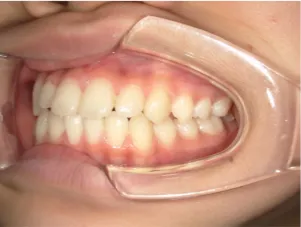

治療前①小2:8y1m 初診

治療中➁小3:9y8m QH、BH、前歯並び替え終了